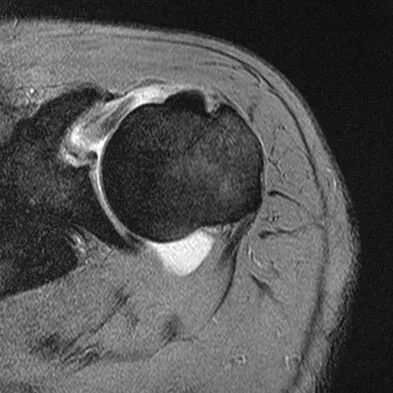

A 39-year-old man has anterior shoulder pain after landing on his abducted left shoulder while playing softball. Examination reveals a stable glenohumeral joint, pain on passive external rotation of greater than 25 degrees, and pain and weakness on belly press (Napoleon's) test. An MRI scan is shown in Figure 32. To provide maximum pain relief and return of function, management should include

Explanation